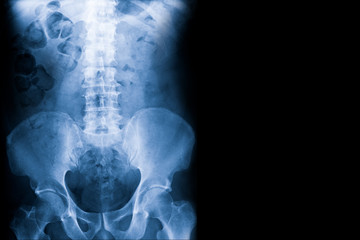

腰椎分離症は、腰椎(背骨の腰部分)の**椎弓(ついきゅう)**と呼ばれる部分に疲労骨折が起こる疾患です。 特に成長期の子どもや10代のスポーツ選手に多くみられます多くの場合、第5瞬間(L5)に発生し、適切な治療を受けないと慢性腰痛や運動制限を伴う可能性があります。

X線検査(レントゲン)

• 分離症の診断に最も一般的な方法です。

• ドームの横方向(側面像)や斜め方向(斜位像)の撮影を行い、椎弓部分に亀裂や骨の離開がないか確認します。

• 特に斜位像では「スコティドッグの首輪」状態の骨折線が特徴的に見られます。